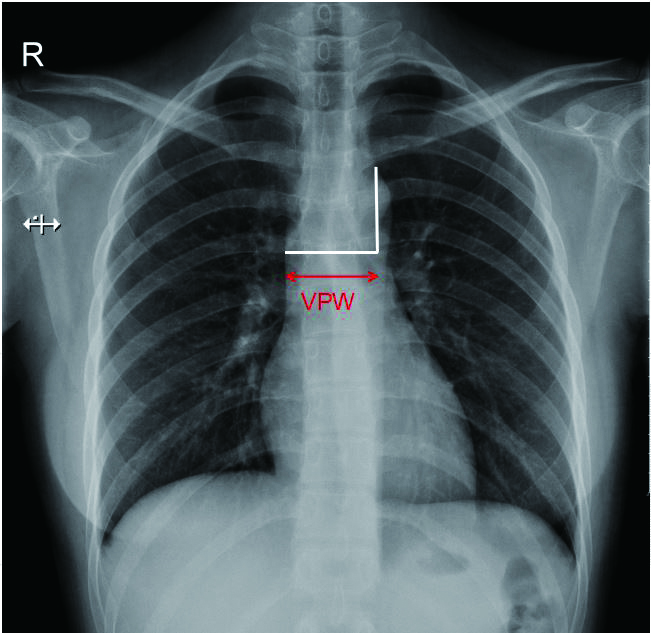

2 血管蒂宽度的测量血管蒂宽度的测量可分为两步:首先从左锁骨下动脉外缘起点开始向下画一条垂直线,然后确认上腔静脉与右主支气管的重叠点,该重叠点到垂直线的水平距离就是血管蒂宽度(图 1)。Milne等[10]报道的正常人直立后前位胸片上VPW为(48±5)mm,仰卧后前位胸片上VPW可增加至58~64 mm,或增加近20%。

| 图 1 血管蒂宽度(VPW)的测量方法(首先从左锁骨下动脉外缘起点开始向下画一条垂直线,然后确认上腔静脉与右主支气管的重叠点,该重叠点到垂直线的水平距离即为VPW) |